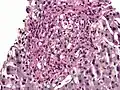

Histoplasma. PAS diastase stain. -

Histoplasma in a granuloma. PAS diastase stain.